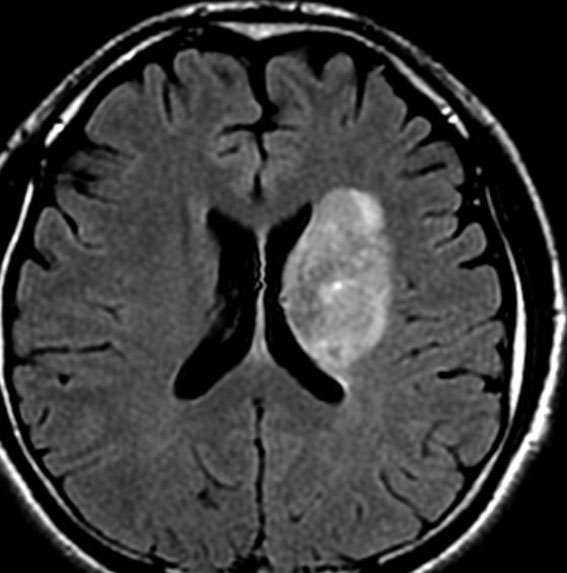

放射線治療終了後22日目

放射線治療前と大差がない所見です。左はガドリニウム増強MRI,右はFLIAR(フレア) 画像。

放射線治療後7週目

フレア画像です。腫瘍サイズが増大しています。もともと腫瘍周辺浮腫はなかったのですが大脳基底核と視床に浮腫が出現しています。スード・プログレッションの始まりです。